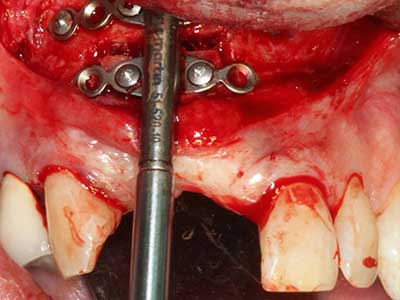

La piezochirurgia presenta altri vantaggi per quanto riguarda la raccolta di blocchi ossei. Oltre all'elevata precisione dell'osteotomia appena descritta, l'utilizzo di puntine per sega molto sottili permette di minimizzare in maniera significativa la perdita di materiale. È molto probabile che si verifichi una maggiore perdita di materiale durante la raccolta utilizzando puntine di strumenti più spessi, in particolare delle frese Lindemann (Lakshmiganthan, Gokulanathan et al. 2012). La separazione basale, necessaria in particolare per i trapianti di blocchi nella zona retromolare, viene semplificata grazie a seghe specificatamente progettate di forma rettangolare; di conseguenza la piezochirurgia è considerata una procedura precisa, semplice e sicura per la raccolta di blocchi di osso nella zona retromolare (Happe 2007) (figg. 1-12).

Indicazione: incisione ossea

Il tessuto osseo non è semplicemente una struttura minerale, ma contiene anche una percentuale significativa di fibre di collagene. Ciò significa che non possiede solo una buona forza di compressione, ma anche un certo livello di flessibilità che è possibile sfruttare durante l'esecuzione degli accrescimenti di osso. Nella procedura di espansione classica con incisione ossea, la cresta alveolare atrofizzata viene incisa longitudinalmente ed espansa con cautela dopo aver raggiunto una profondità di osteotomia adeguata (figg. 13-16), idealmente senza una sostanziale rimozione del periostio (Brugnami, Caiazzo et al. 2014, Stricker, Fleiner et al. 2014). I sistemi a piastra e vite con distanza di espansione incrementale si sono dimostrati efficaci nella separazione delle due lamelle ossee restando al di sotto della soglia di frattura. In generale, sono richieste larghezze dell'osso residuo di almeno 3-4 mm (Chiapasco, Zaniboni et al. 2006) per garantire un'adeguata flessibilità e una copertura sufficiente dell'osso per gli impianti futuri. Se necessario, un'osteotomia di rilascio verticale su uno o più lati può migliorare la flessibilità. Una combinazione con ulteriori tecniche di accrescimento, in particolare dal lato buccale, è stata descritta come un'alternativa alla tecnica classica.

La procedura di incisione è particolarmente atraumatica e non comporta una perdita significativa di dimensione durante l'utilizzo delle seghe piezoelettriche, così come non si notano differenze rilevanti tra impianti in mandibole incise e impianti in una cresta alveolare senza deficit osseo (Chiapasco, Zaniboni et al. 2006, Danza, Guidi et al. 2009). Una sufficiente irrigazione continua è essenziale, tuttavia, in particolare con incisione profonda e localmente ristretta, per prevenire la sollecitazione termica nelle regioni apicali dell'osteotomia.